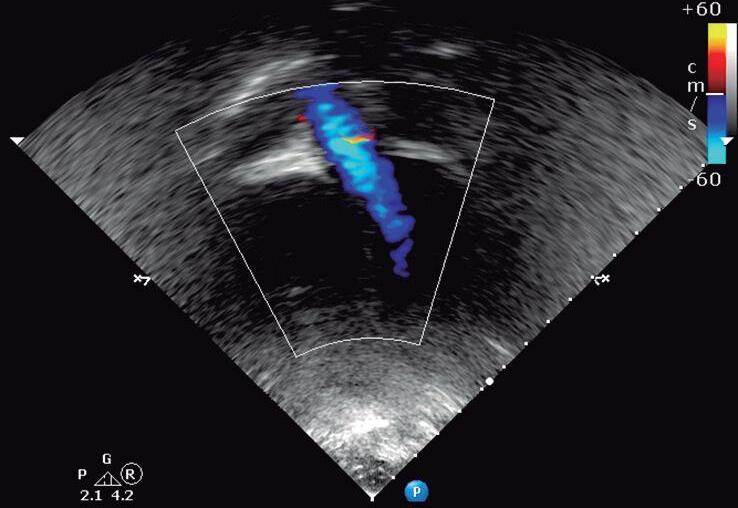

O plano do “canal arterial” ou “ductal” é obtido posicionando-se o transdutor infraclavicular à esquerda com o index às “12 horas” (plano paraesternal alto), permitindo pesquisar se o canal arterial (ductus arteriosus) está pérvio ou não e, quando presente, mensura seu diâmetro (▶ Vídeo 1-22). Nessa avaliação, o Doppler colorido é muito útil possibilitando a detecção de canais pequenos, além da direção do shunt (Fig. 1-8 e ▶ Vídeo 1-23).

Fig. 1-8. Plano paraesternal alto (plano do “canal arterial”) com Doppler colorido. Ao: aorta; AP: artéria pulmonar.